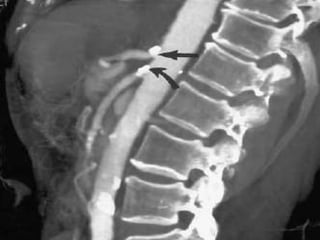

Sagittal subvolume and coronal subvolume MIP images show severe stenosis of

the celiac, superior mesenteric and inferior mesenteric arteries.

• 100.

Sagittal subvolume andcoronal subvolume MIP images show severe stenosis of the celiac, superior mesenteric and inferior mesenteric arteries.